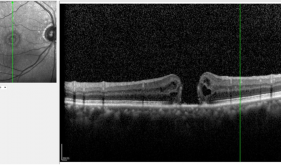

眼底病科是绵阳市医学甲级重点专科。科室先后派出技术骨干到川大华西医院眼科中心、中山大学眼科中心、北京同仁眼科医院等进修眼底外科(玻切手术)和眼底内科,组成了眼底病专业组及技术专家骨干团队。人才队伍:医护团队现有20余人,其中主任医师1人,副主任医师4人,主治医师5人,医师3人,硕博士6人。先进设备:配备了德国蔡司700型眼科手术显微镜4台、美国科医人532眼底激光治疗仪2台、美国爱尔康27G玻切手术系统2台,海德堡眼底血管...